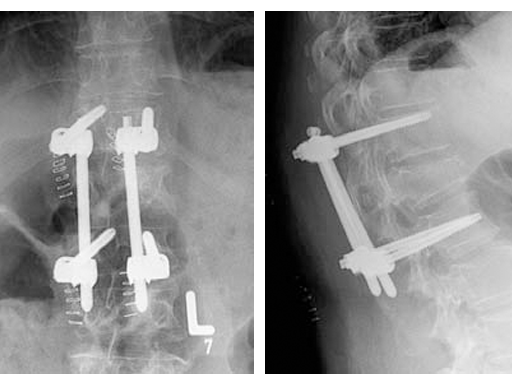

The incomplete burst fracture associated with the destruction of the intervertebral disc resulted in the planning of a two staged approach. In a first immediate surgery, the unstable fracture was stabilized by posterior percutaneous AP and lateral preoperative CT scans. fixation. In a second surgery, a cranial hemi-vertebrectomy was performed. Reconstruction was done using an autologous iliac crest bone graft and a plate to achieve a mono-segmental fusion.

Based on the preoperative analysis and the surgical plan, the patient was positioned supine for the first surgery and the fracture was stabilized with a bridging construct (T12-L2) from posterior. Due to the ruptured disc, an anterior reconstruction of the spine was planned for a later stage surgery. The posterior stabilization was considered to be sufficient to bridge the fracture and time between both surgeries.

As a result of the ruptured disc and the fractured superior endplate, a hemivertebrectomy was performed and reconstruction was performed using an autologous iliac crest bone graft. To keep the graft in place and to allow for early posterior implant removal, an ArcoFix plate was used, allowing for slight compression as well as final sagittal reconstruction.

The hemivertebrectomy and the placement of the bone graft and ArcoFix plate were performed applying thorascopically assisted surgical technique.